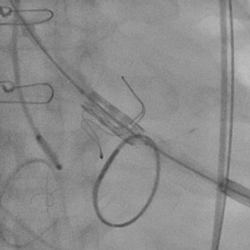

黄焕雷主任带领具有丰富经验的心脏麻醉医师、体外循环师、超声心动图医师、手术室、心外重症监护室、心脏导管室多学科团队,联合心内科专家谢年谨主任,为蔡先生实施小切口下、介入途径的主动脉瓣“瓣中瓣”、二尖瓣“环中瓣”的同期植入手术:黄主任首先在患者左前胸做一小切口,暴露患者的心尖,在跳动的心脏上“绣”上荷包作为介入导管、瓣膜的植入“门户”;随后,黄焕雷主任在超声心动图、放射透视的引导下,将一钢针在患者心尖“扎”入患者心脏内,为之后的瓣膜植入作为引导,具体来说就是将预先选择适合患者大小的生物瓣膜折叠、压缩入细长的输送管道内,好比将瓣膜这一“弹头”安放在输送导管这颗精准制导的“火箭”上,而黄主任的双手则控制这一精准发射和制导,再将瓣膜输送到主动脉合适的位置后释放,新的主动脉瓣便牢固地“卡”在了原有的主动脉瓣架内。经过透视和超声心动图评估,主动脉瓣位置合适,开放、闭合功能良好。随后,黄主任通过这一根钢针和输送导管,利用类似的方式,调整“火箭”的发射轨道,在原有二尖瓣人工瓣环内植入预先选择好大小的二尖瓣生物瓣膜,经过影像学方式评估,新植入的二尖瓣生物瓣工作良好。

术后左室造影